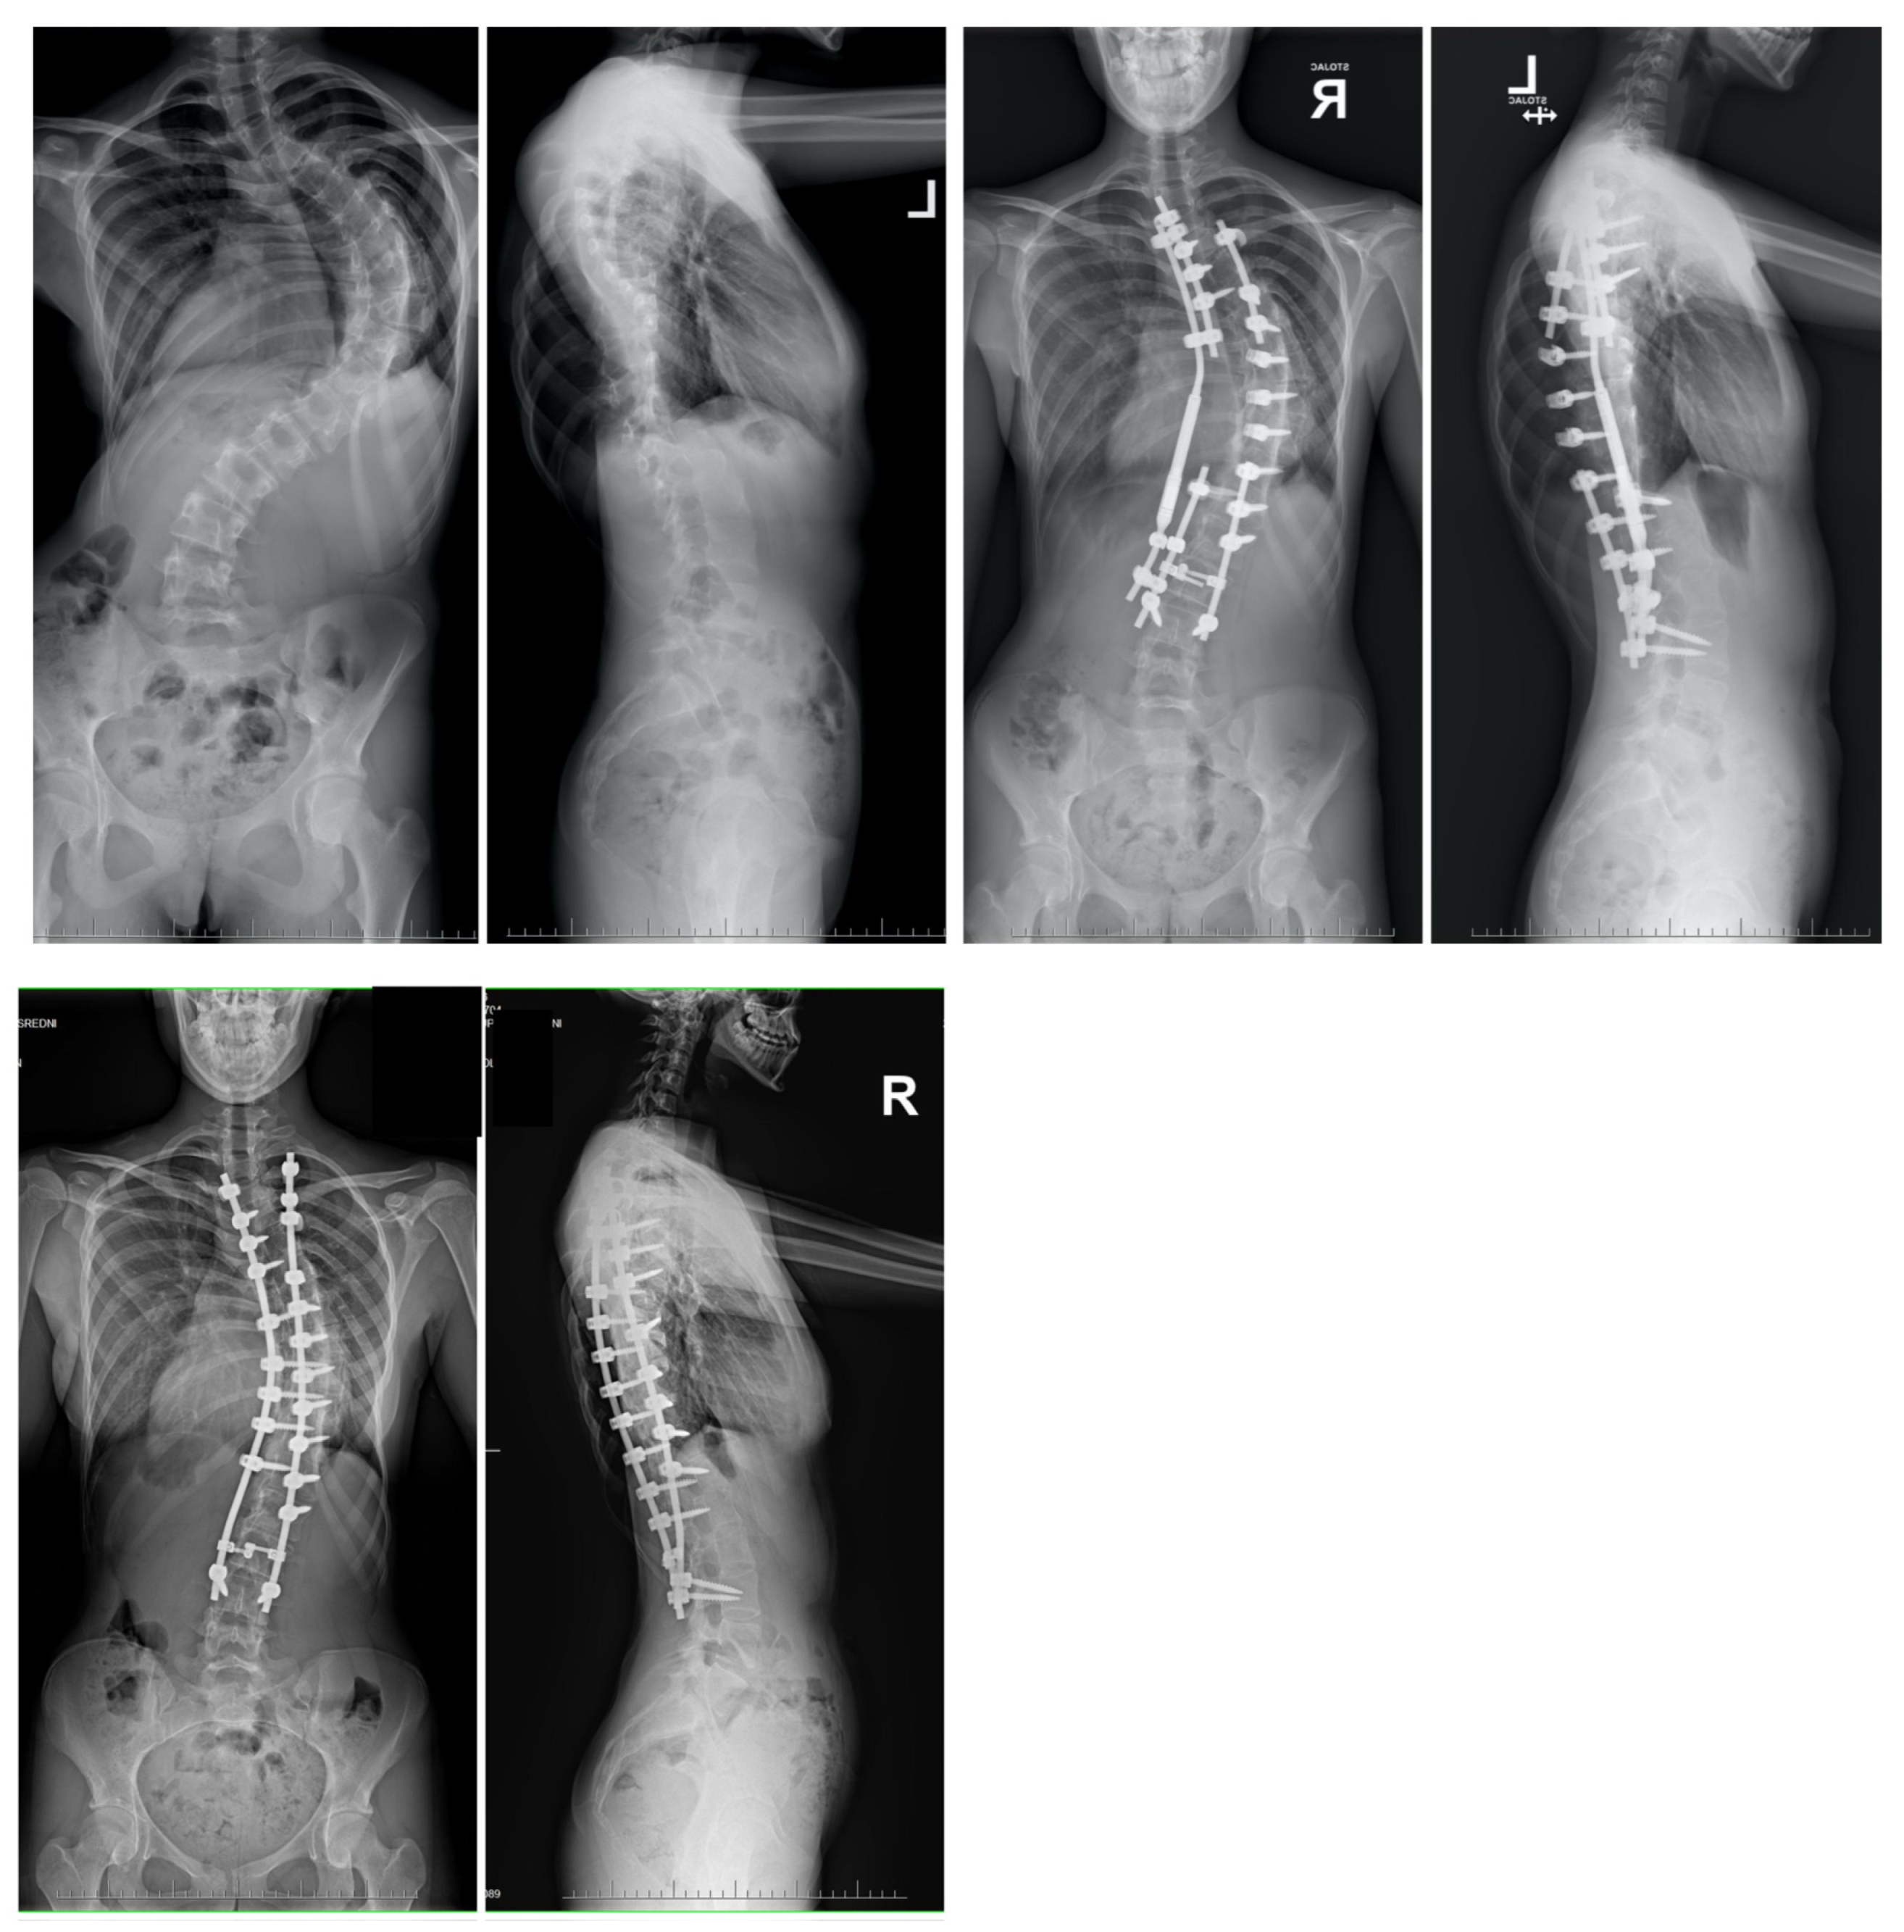

2. Material and Methods

8. Temporary Internal Distraction Rods

11. Author’s Preferred Technique